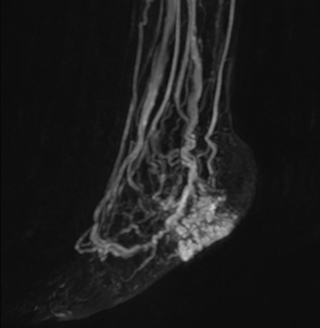

mDIXON MRA in chest

Performed on Ingenia Ambition. FOV 430 mm, voxels 1.3 x 1.3 x3.0 mm, 130 slices, Breath hold 16.6 sec